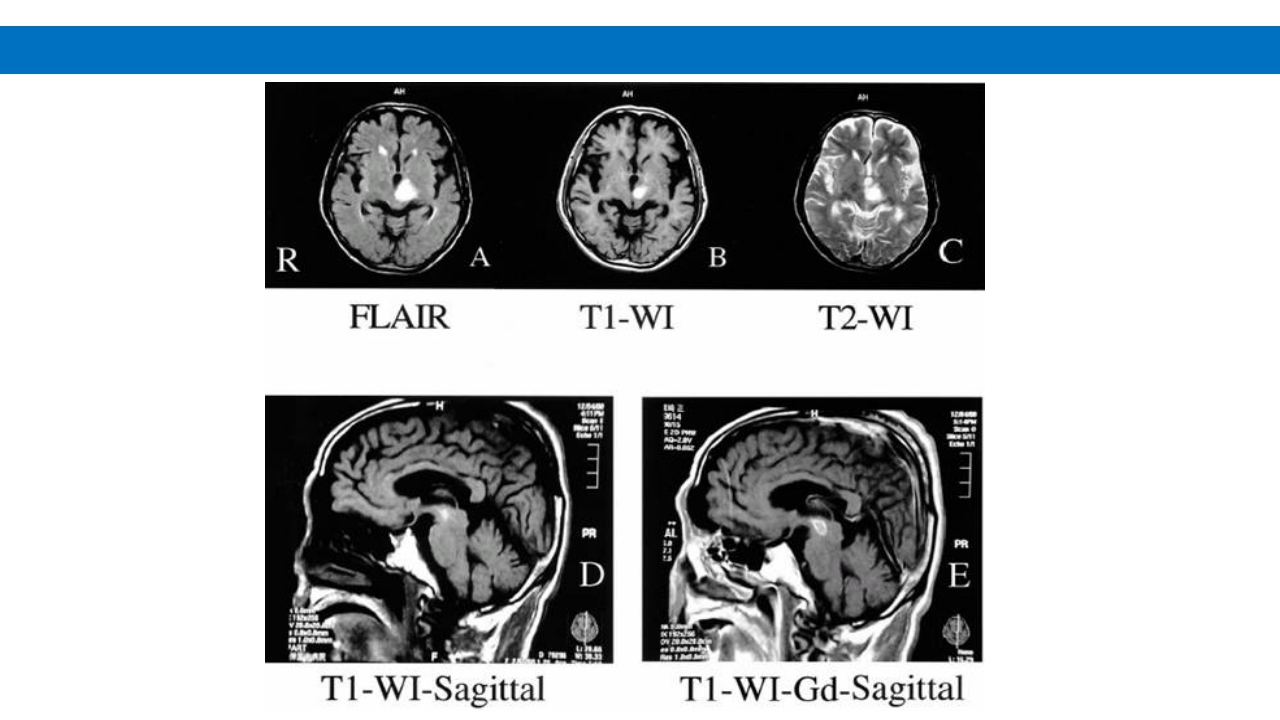

颅脑损伤的并发症及后遗症 讲解人:xxx 20XX年x月x日 1.颅骨骨髓炎 病因:为头皮软组织、中耳、乳突和副鼻窦等处炎性感染而经导 血管侵入颅骨内或颅脑开放伤感染所引起,亦可由菌血症后发生 的细菌栓子由血运转移至颅骨内。 影像学表现: 头部CT: 1.表现为不规则的蜂窝状骨质破坏区,主要位于板障,亦可累 及内外板。 2.破坏区内可见高密度的米粒状细小的高密度死骨。 3.周边可见骨质硬化增生,颅板外无骨膜反应。 4.局部的头皮可见软组织肿胀。 头部MRI: 由于受累部位细胞成分和水量增多,T1WI为低信号, T2WI为高信号,急性期边界不清,慢性期病灶局限, 边界清晰。MRI显示骨质破坏没有CT效果好。 治疗: 除应用抗菌药物控制感染外,当感染局限或已有死骨形成后, 应行手术切除感染...